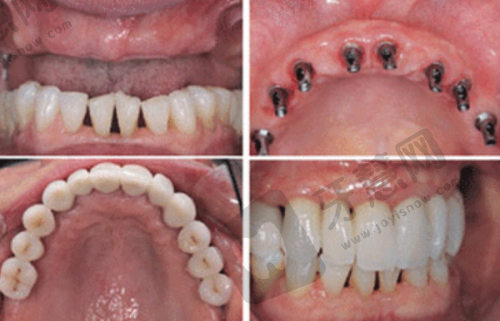

李时顺医生:作为总院种植科核心力量,精通即刻种植、骨增量技术及全口半口无牙颌种植修复,尤其擅长处理牙槽骨吸收导致的骨量不足问题。曾为牙槽骨吸收重度的老人成功解决缺牙问题。

孟岩医生:专注于单颗、多颗及全口种植领域,在美学种植修复方面造诣颇深。擅用动态导航技术规划种植路径,针对半口/全口缺牙患者,常采用ALL - ON - 4/6即刻负重技术,实现当天戴牙的快速修复。曾为商务人士采用该技术,当天种牙当天就能吃东西。

众多成功实例见证实力:北京中诺口腔医院有特别多种植牙成功实例。老大爷牙齿全掉光,刘忠祥医生为其制定全口种植方案,术后能正常吃饭,身体修复健康。年轻女士前牙缺失,潘火青医生为其进行前牙美学区种植修复,牙齿美观,女士变得自信。